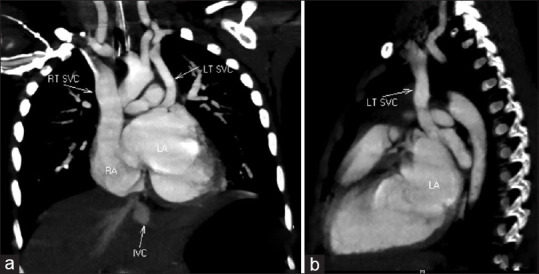

Coronary sinus (CS) defects are rare congenital cardiac anomalies that occur in isolation or with other congenital heart diseases. Persistent left superior vena cava (LSVC) is a relatively common entity that usually drains into the CS, is of no hemodynamic consequence, and is easily diagnosed on echocardiography by a dilated CS and an antegrade flow toward the heart. However, a combination of LSVC and CS defect may reverse its flow direction and CS dilation may be absent. In the absence of echocardiographic clues, the reversed flow can be easily misdiagnosed for other structures such as the more common vertical vein of anomalous pulmonary venous connection or the rarer levoatrial cardinal vein. Here, we report a 2-year-old boy with ventricular septal defect, patent ductus arteriosus, absent CS, and a persistent LSVC with retrograde flow producing a hemodynamically significant pretricuspid left-to-right shunt along with its diagnostic challenges. He underwent successful surgical closure of these defects and had been asymptomatic on follow-up.